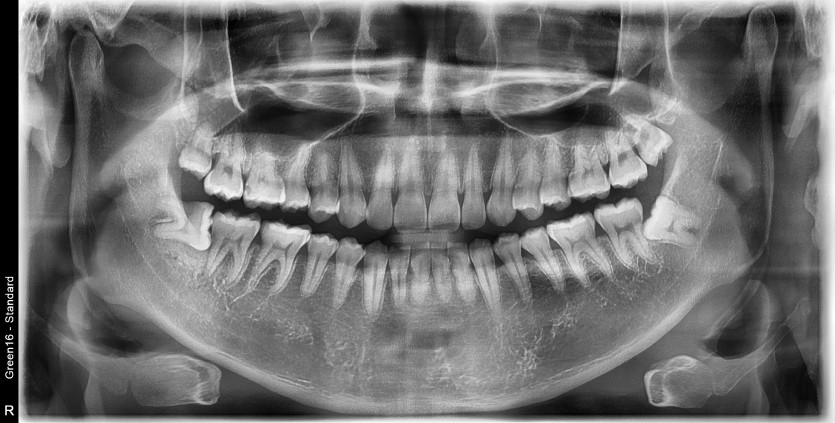

#48 사랑니 발치

구강 외과 전문의가 당일 발치했습니다.